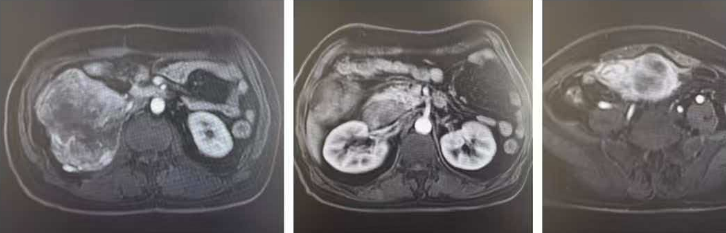

病例 1:63 岁男性患者,2 年前在当地医院做过右侧腹膜后脂肪肉瘤切除手术,之后肿瘤复发。复查发现,腹腔里有两处大肿瘤,一处 15cm,已经侵犯了右肾、右半结肠;另一处 10cm,侵犯了小肠,患者已经吃不下饭,再次手术的复发风险极高。经过多学科团队(MDT)综合评估后,先由放疗科卢宁宁主任团队完成新辅助放疗,再由泌尿外科王明帅主任团队,把肿瘤和被侵犯的小肠、右肾、右半结肠等组织整块完整切除,最大程度避免癌细胞残留。整个手术只用了 2 个小时,出血量不到 200ml,患者术后恢复非常顺利,半年后复查,没有发现肿瘤复发。

术前腹部核磁片子